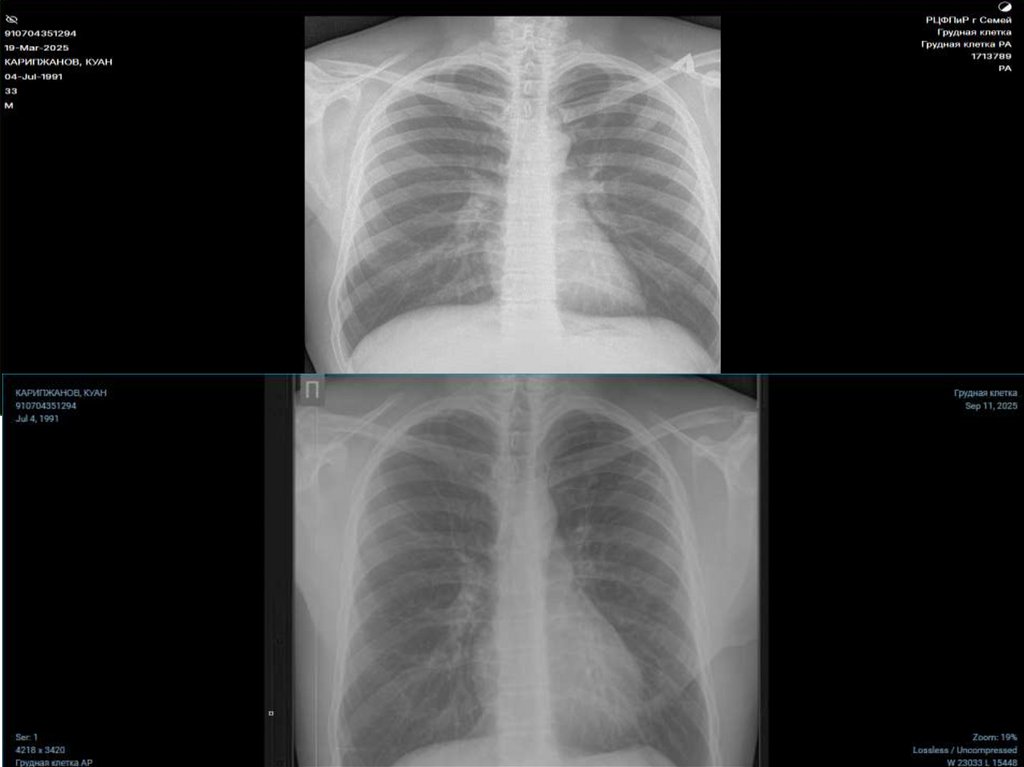

• Меньщиков Дмитрий Дмитриевич

• 26.10.1964

• Диссиминированный хронический туберкулез

легких в фазе распада МТ(+) ЛЧТБ НС I

категория IА группа ДУ обращение

запущенный случай

10. Рентгенография ОГК от 26.06.2024г заключение: ДТЛ МТ+

Рентгенография ОГК от

26.06.2024г заключение:

ДТЛ МТ+

27.08.2024г заключение: ДТЛ

МТ +

• Меньщиков

Дмитрий

Дмитриевич

• Диссиминирован

ный

хронический

туберкулез

легких в фазе

распада МТ(+)

ЛЧТБ НС I

категория IА

группа ДУ.

Обзорная

Рентгенография

ОГК от

20.01.2025г